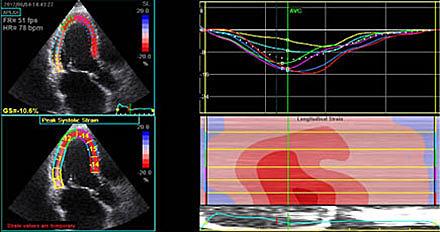

Monitorering af venstre ventrikels pumpefunktion i et behandlingsforløb kan foretages med ekkokardiografi, multiple-gated acquisition (MUGA)-skanning eller MR-skanning. Undersøgelserne har hver for sig fordele og ulemper (Tabel 4), men serielle bestemmelser af hjertets pumpefunktion ved en metode med beskeden undersøgelses- og observatørvariation vil være at foretrække. De tre undersøgelsesmodaliteter har ikke samme normalreference, hvorfor resultater fra forskellige undersøgelsestyper ikke umiddelbart kan sammenlignes [24, 25].

Todimensional ekkokardiografi er behæftet med en betydelig observatørvariation, som mindskes ved tredimensional ekkokardiografi og/eller anvendelse af kontraststof [25]. Der er fortsat beskeden evidens for anvendelse af avancerede ekkokardiografiske mål for diastolisk dysfunktion samt myokardiets forkortningsfraktion (global longitudinal strain) til identifikation af tidlige tegn på kardiotoksisitet, og disse mål benyttes ikke rutinemæssigt i dansk klinisk praksis [26]. MUGA-skanningens begrænsning er primært, at der ikke opnås oplysninger om øvrige kardiale forhold, som kan have betydning for pumpefunktionen, som f.eks. klappatologi, regional myokardiefunktion og perikardiesygdomme. MR-skanning anses for guldstandarden pga. den høje billedmæssige opløsning, der giver mulighed for høj præcision i vurderingen af både anatomiske og funktionelle forhold, men tilgængeligheden er fortsat begrænset [24, 25].